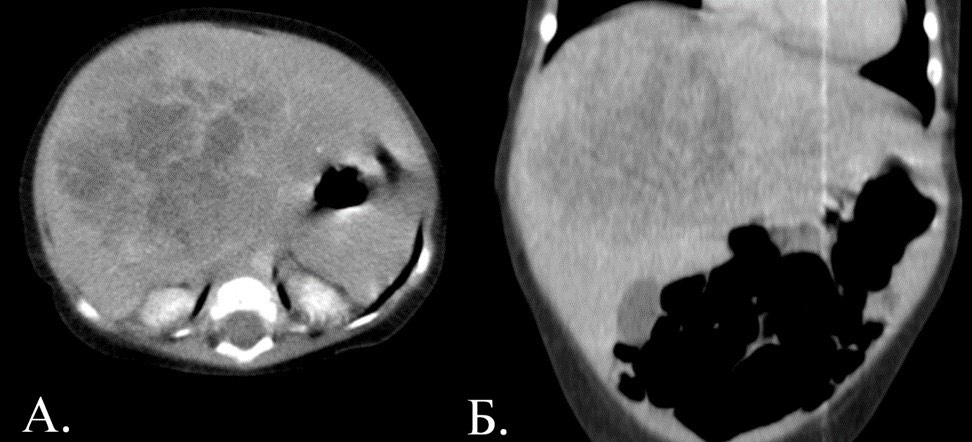

1884. Пациенту 1 год, лихорадка в 4 месяца, на УЗИ — образование неоднородной эхоструктуры, смешанной эхогенности, альфафетопротеин — 124983 ме/мл, на КТ органов брюшной полости определяется объемное образование правой доли печени, выполнена магнитно-резонансная томография органов брюшной полости, рентгенологическая картина соответствует